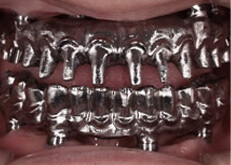

③ 安全で確実なオペときれいな仕上がり

オールオン4において最も重要な要素であるインプラントポジション。 当初はフリーハンドでインプラントの埋入を行っておりましたが、現在ではほとんどのケースでガイデッドサージェリーによる埋入を行っております。その目的は数多くありますが、患者様の負担を最小限に抑える事と、アクセスホール(ストラクチャーをインプラントに固定する為のねじ穴)をコントロールする事でとてもきれいな仕上がりとなります。

ガイデッドサージェリー

サージカルテンプレート